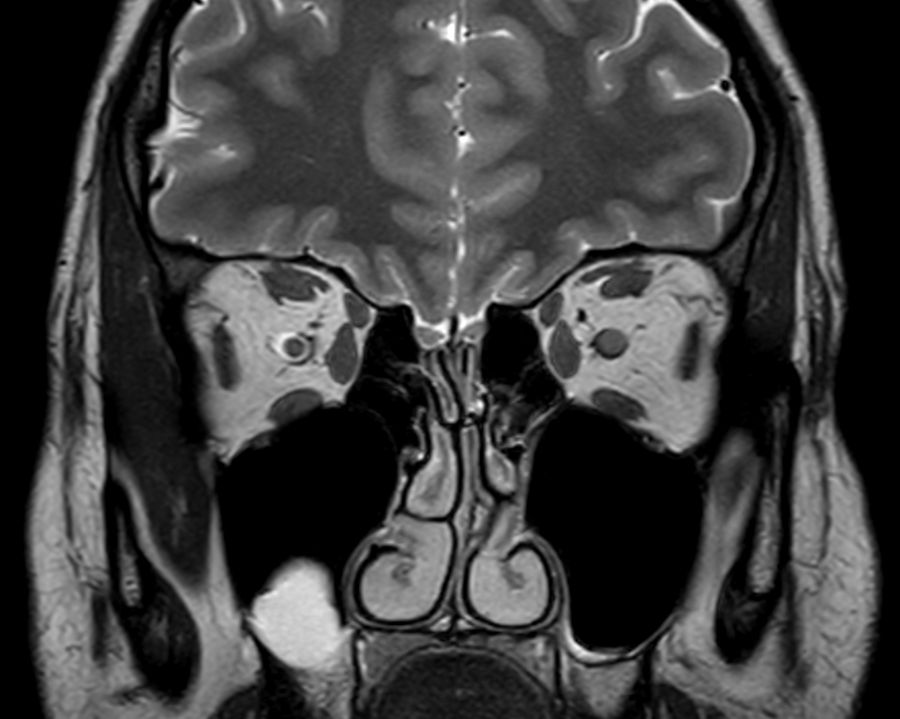

3D VIEW - T2w FatSat (coronal reformat)

3D VIEW - T2w FLAIR (coronal reformat)

Coronal T2w TSE mDIXON (In-Phase)

Coronal T2w TSE mDIXON (Water only)